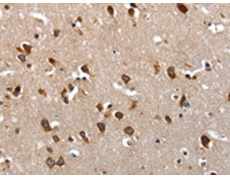

IHC positive control: |

Human brain and Human colon cancer |